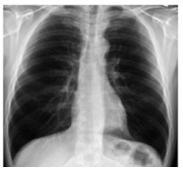

The ROI was extracted from the CXR image to extract the desired information from the image. The ROI area is outlined by a locality primarily covering the lung region to obtain vital information. The ROI area is marked by a rectangle and with the help of logical indexing, the inside area of the region is extracted. Table 2 shows the different pre-processing stages. For example, the unwanted marks in the normal and COVID-19 groups were removed in the first stage (ROI). The CXR images utilized in this examination were gathered from three different sources, which may differ in feature or dimensions. To address this issue, all the images were resized to 300 × 300 before applying any operation on the images. The following Table 2 shows the comparison of original and COVID-19 images.

Table 2. Proposed image processing: original, ROI, and RGB to gray.

Image CategoryOriginalROIRGB to GRAY

NormalElectronics 11 04053 i001Electronics 11 04053 i002Electronics 11 04053 i003

COVID-19Electronics 11 04053 i004Electronics 11 04053 i005Electronics 11 04053 i006